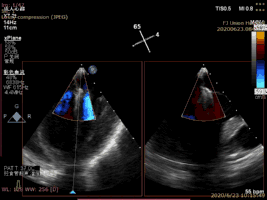

病例1术后二尖瓣反流为轻度